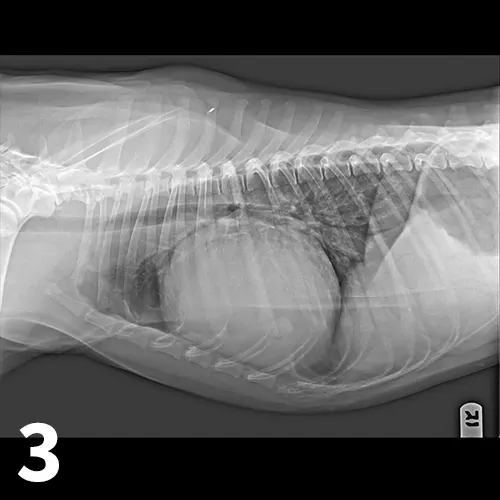

• Echocardiography confirms an echo-free space between the heart and the pericardium (Figure 1), may show cardiac tamponade (Figure 2), and may detect mass lesions.

Short-axis (hammerhead) view showing the left ventricle (LV), interventricular septum (IVS), and right ventricle (RV) surrounded by pericardial effusion (PE), which can be seen within the bright pericardium (asterisk). A short-axis view of the heart allows visualization of pericardial effusion by identifying an anechoic ring of fluid within the bright pericardium, helping differentiate the fluid from pleural effusion. Image courtesy of Meriel LeSueur, DVM